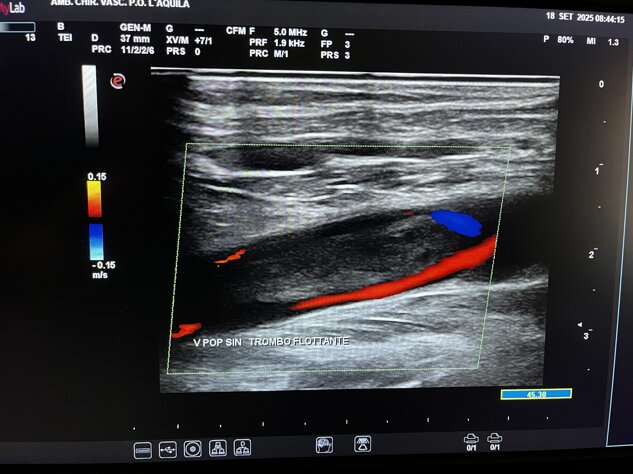

Ecocolordoppler

Tromboembolia polmonare

massiva in paziente con

trombo nella vena poplitea